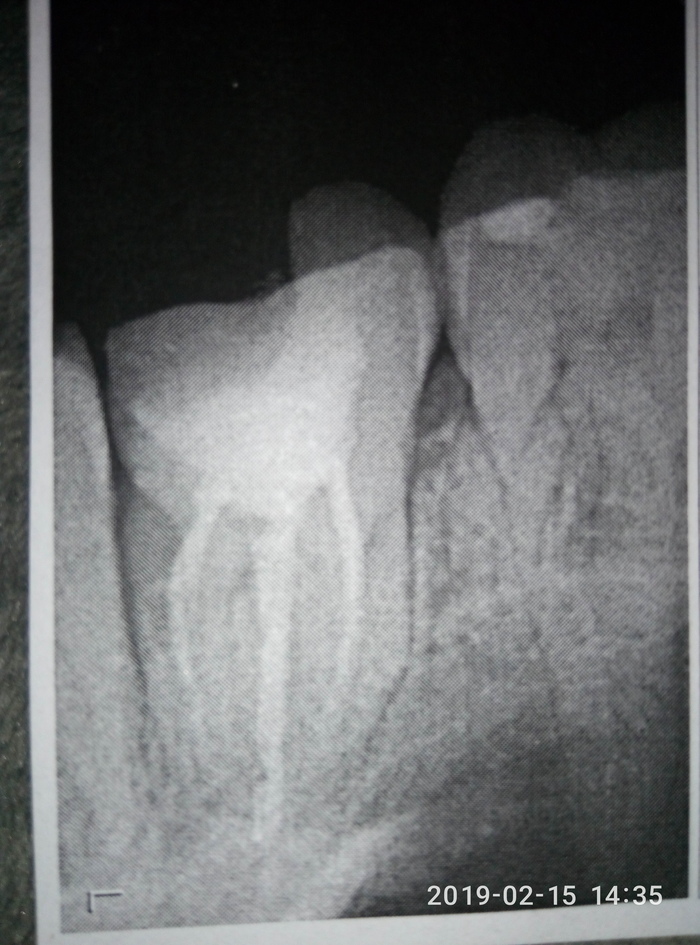

В дополнение к https://pikabu.ru/story/plomba_plomba_6504227

В кратце: в частной клинике хотели зуб удалить из-за воспаления корня, в заводской стоматологии зуб спасли, но он развалился спустя пол года. Сейчас будут ставить разборную вкладку + коронка. Итого бюджет за зуб перевалил за 20к :/

P. S еле взял снимок. А зачем он тебе? Там все равно никто ничего не поймет, мы тебе зуб спасли, а ты скотина неблагодарная у кого то советоваться собрался. Цирк.